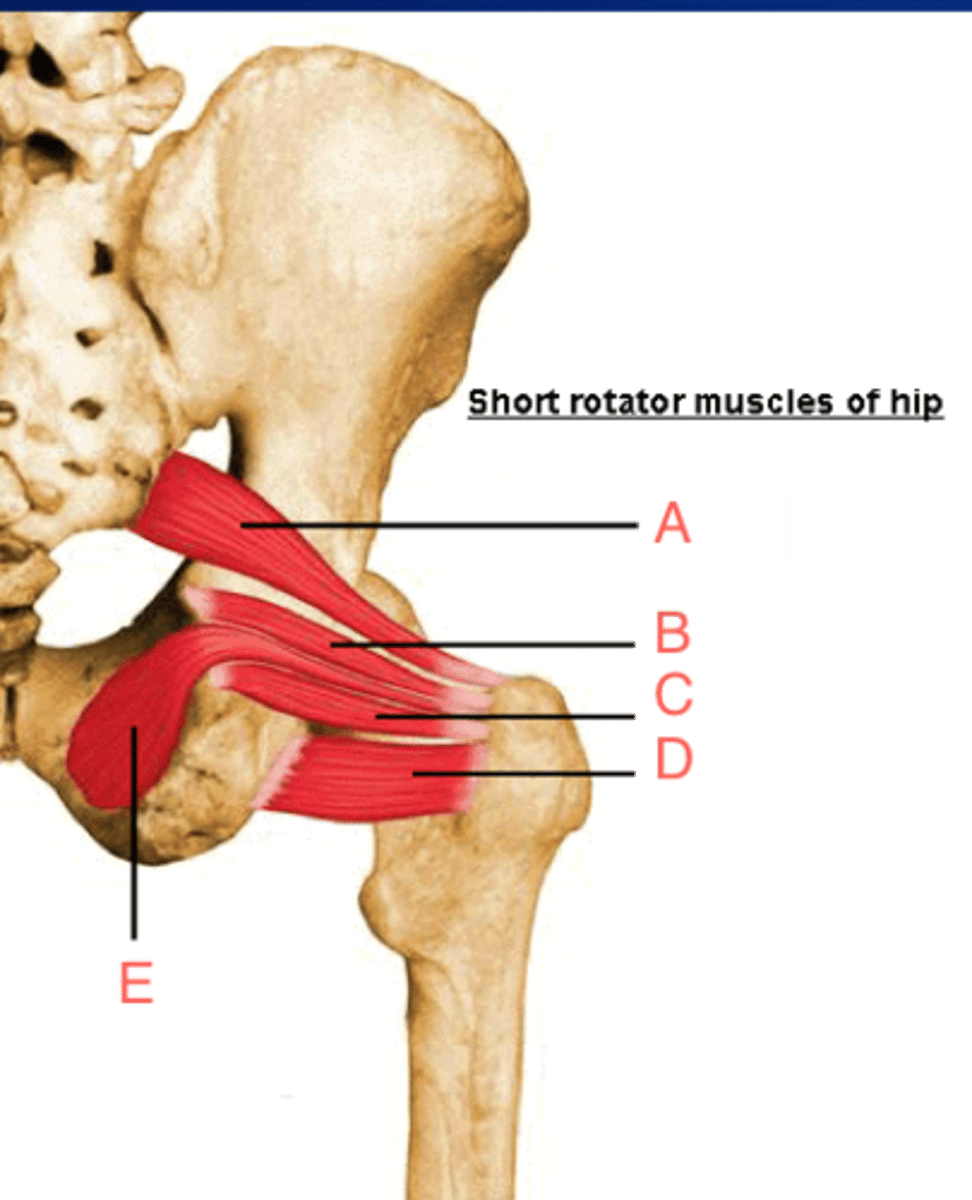

Piriformis m.

Origin: sacrum

Insertion: femur proximal end

Action: abduct, rotate

Obturator internus m.

Origin: obturator foramen edge

Insertion: femur proximal end

Action: abduct, rotate

Sup./inf. gemellus m.

Origin: ischium

Insertion: femur proximal end

Action: abduct, rotate

B and C

Quadratus femoris m.

Origin: ischium

Insertion: femur proximal end

Action: abduct, rotate